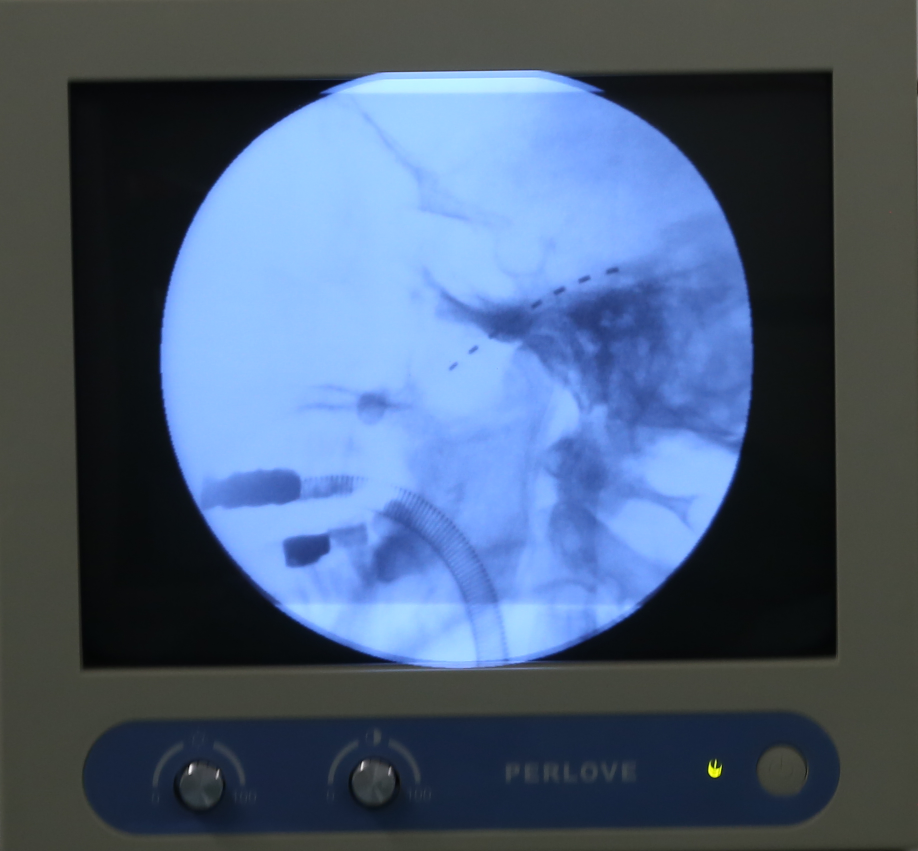

11月27日,四川省人民医院赵冬冬主任联合麻醉手术科,为李大爷实施了院内首例三叉神经半月节电刺激装置植入术。术中X线透视下精确定位,精准穿刺,将电极置入三叉神经节附近,X线透视可见电极置入位置准确,且未出现并发症,手术微创、无痛、安全、有效。